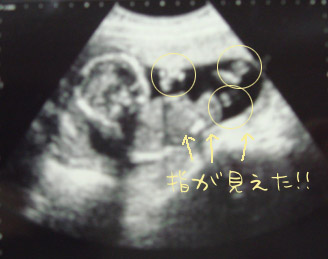

戌の日にいったときのエコー。

はっきりくっきり、手足の指が写真に写っていて驚いた。

でも指の数がしっかり5本確認できないのがちと複雑ww指5本ずつあってくれ